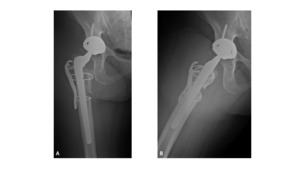

A 63-year-old female presented with recurrent THA instability - verbal consent was obtained for this report. She underwent L2-S1 posterior stabilization with L2-L3 anterior lumbar interbody fusion in May 2002 (Figure 1) and an uncomplicated right THA in April 2007. (Figures 2a-b) Five years following primary THA (July 2011), the patient sustained her first THA dislocation, which was treated with a closed reduction. Between 2011 and 2018, the patient had seven repeat episodes of hip instability – in 2012, one was complicated by a peri-prosthetic femur fracture requiring three revisions and reconstruction with a trochanteric claw plate. She was subsequently diagnosed with a prosthetic joint infection (PJI) which required an antibiotic spacer and subsequent re-implantation three months later. (Figures 3a-b) Following treatment of initial instability and femur fracture, the implants included a size 16 standard taper femoral stem and a 50-mm acetabular shell with 32-mm liner.